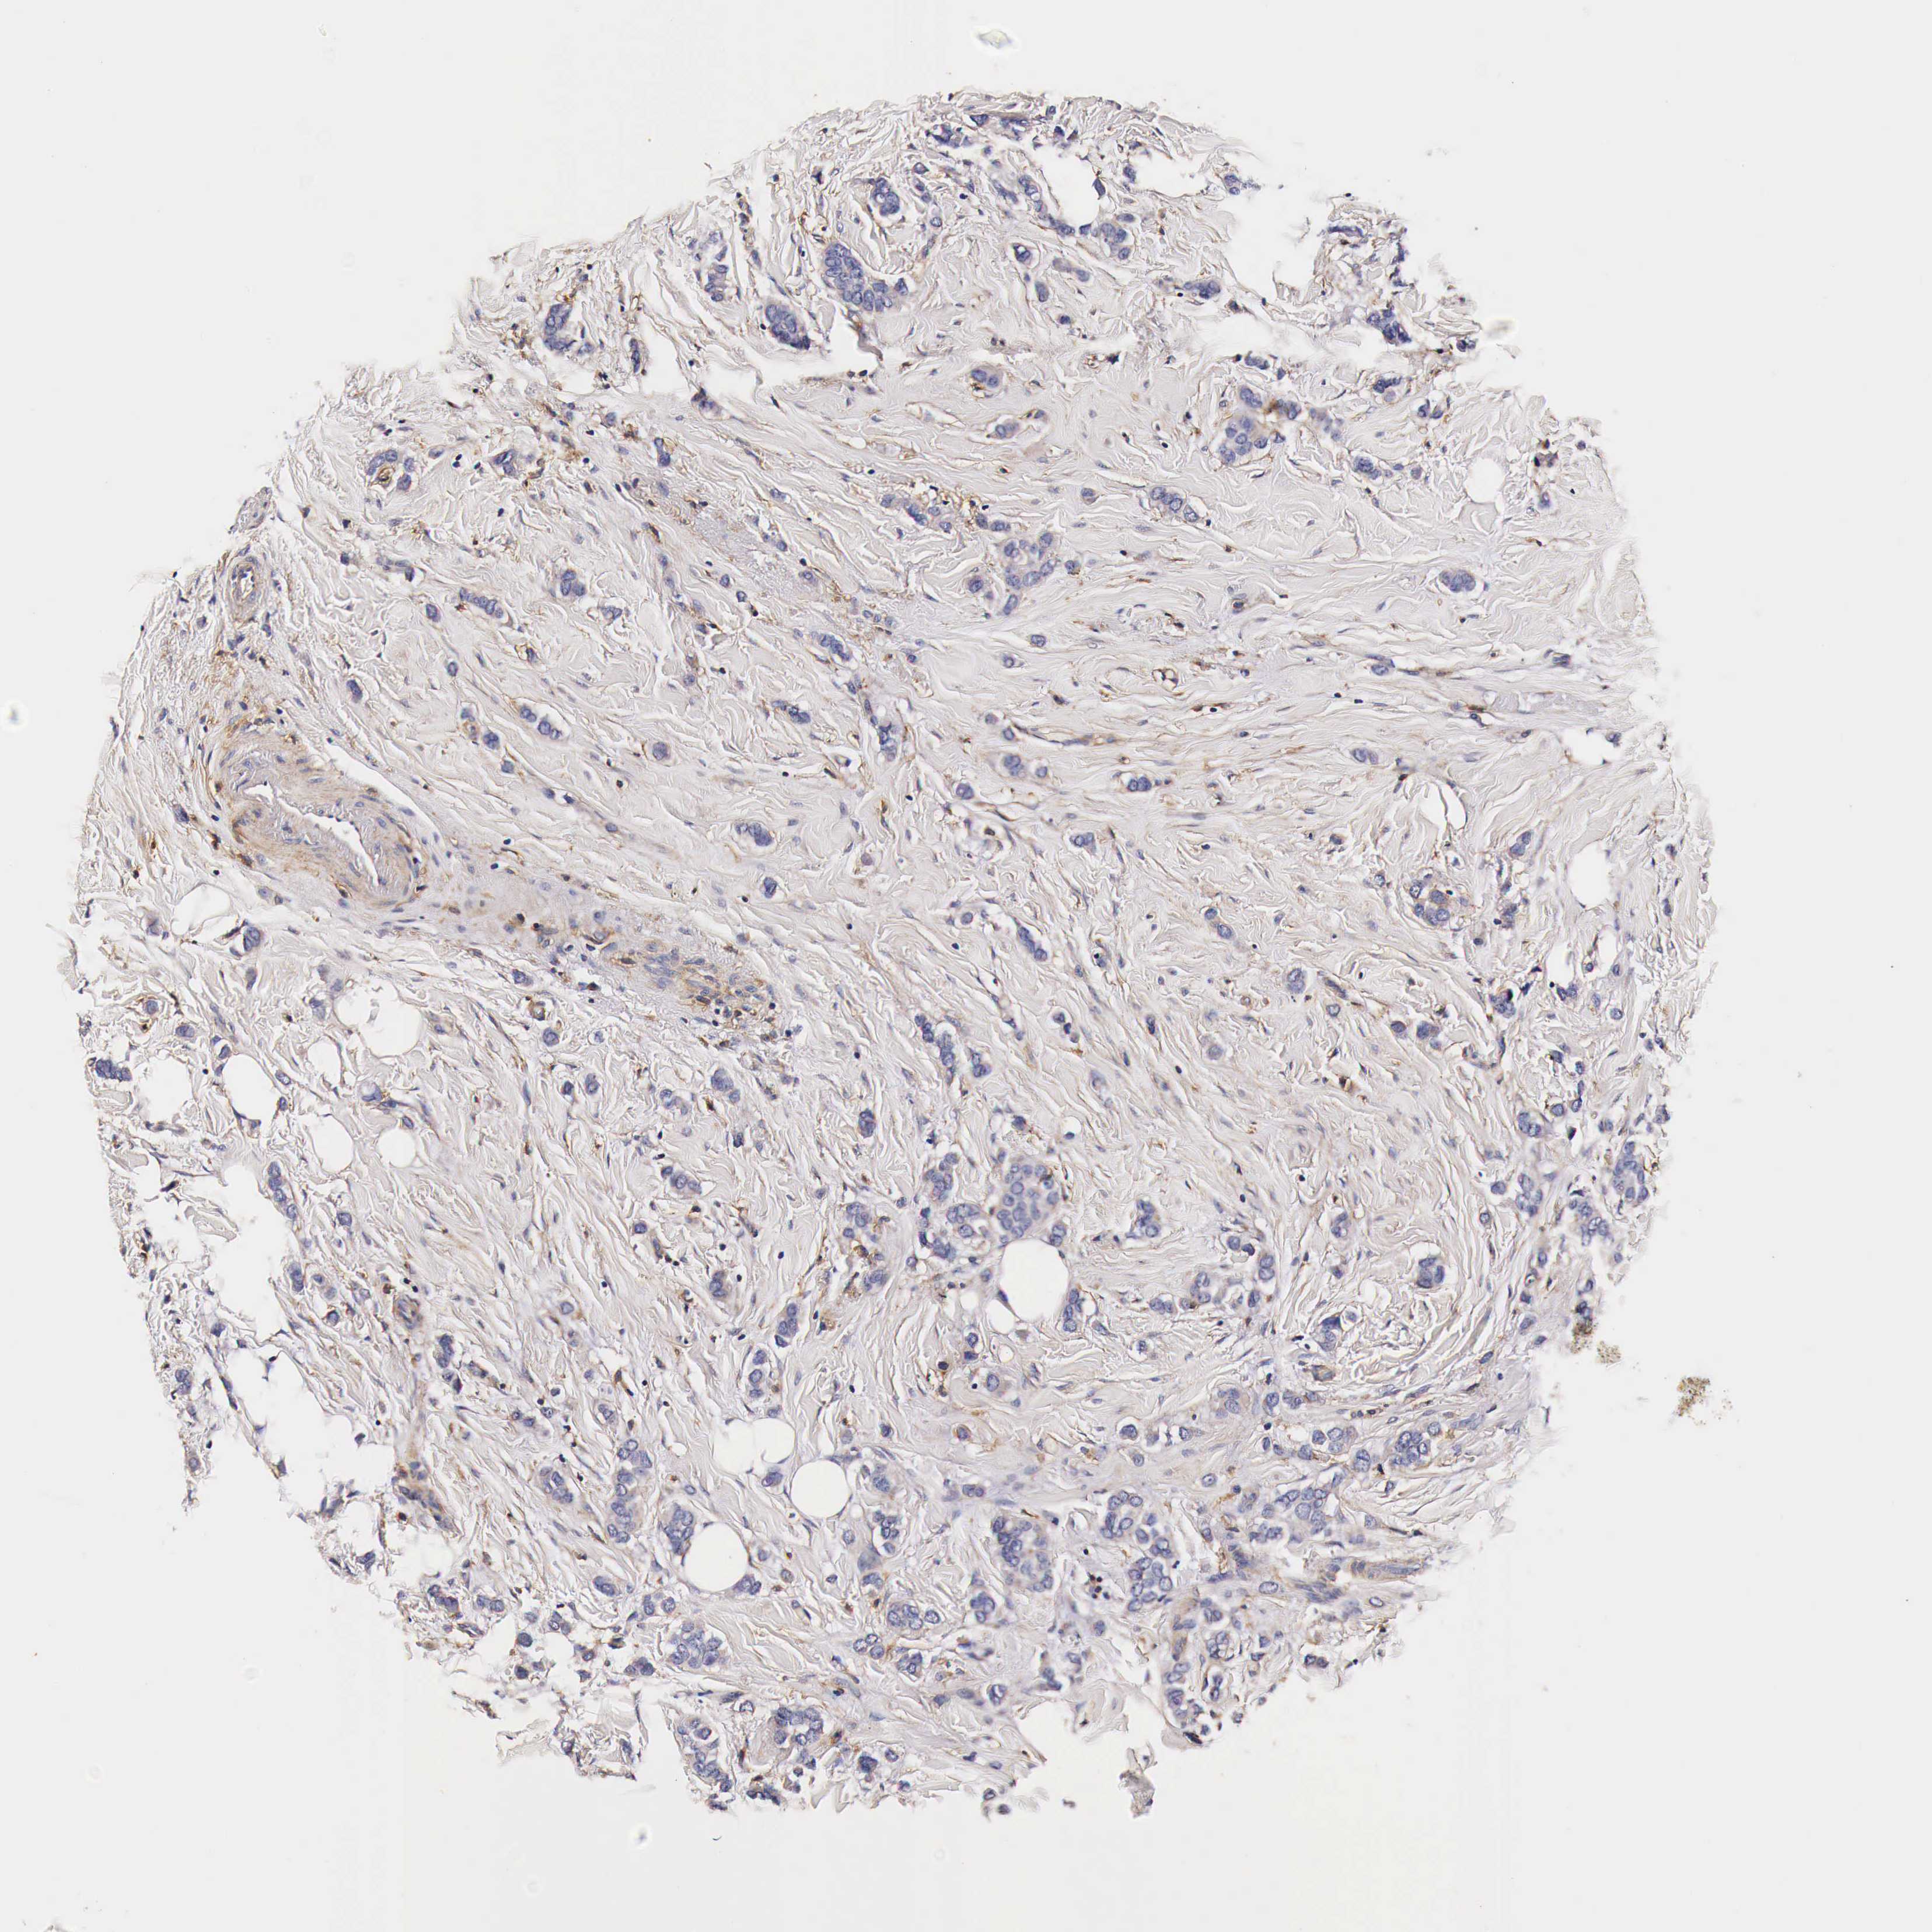

CANCER BREAST CANCER Show tissue menu

BRCA TCGA BRCA VALIDATION PROTEIN EXPRESSION

Breast cancer

Human cancer